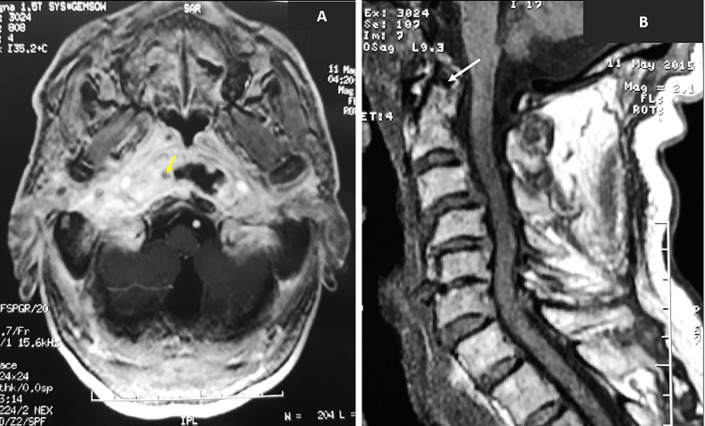

Fungal necrotizing external otitis (NEO) is a rare disease. It is an aggressive and potentially fatal infection. The most commonly reported pathogen is Candida. We aim through this study to share our experience in the management of fungal necrotizing external otitis and discuss its diagnosis tools, anti-fungal treatment choice, and outcomes. We included fifteen patients with diagnosis criteria of fungal NEO; clinical features of NEO with positive culture swabs and/or positive serologic test to a fungal pathogen. The mean age was of 70 years with a prevalence of males. The main symptoms were otalgia (n=15) and otorrhea (n=7). Facial palsy was observed in four cases. Fungal pathogens were Candida(n=10) and Aspergillus (n=5). Complications were observed in eight cases: extension to the temporo-mandibular (n=4), abscess in the retropharyngeal space (n=2), abscess in the parapharyngeal space (n=1) and thrombophlebitis of the internal jugular vein (n=1). Six patients were treated with fluconazole, eight with voriconazole, and one patient with itraconazole. After a mean duration of 52 days of antifungal therapy, fourteen patients have been cured with normalization of the ear symptoms, biological, and imaging features. One patient died of septic shock. No recurrence of the disease was observed after a follow-up of 12 months in all cases.